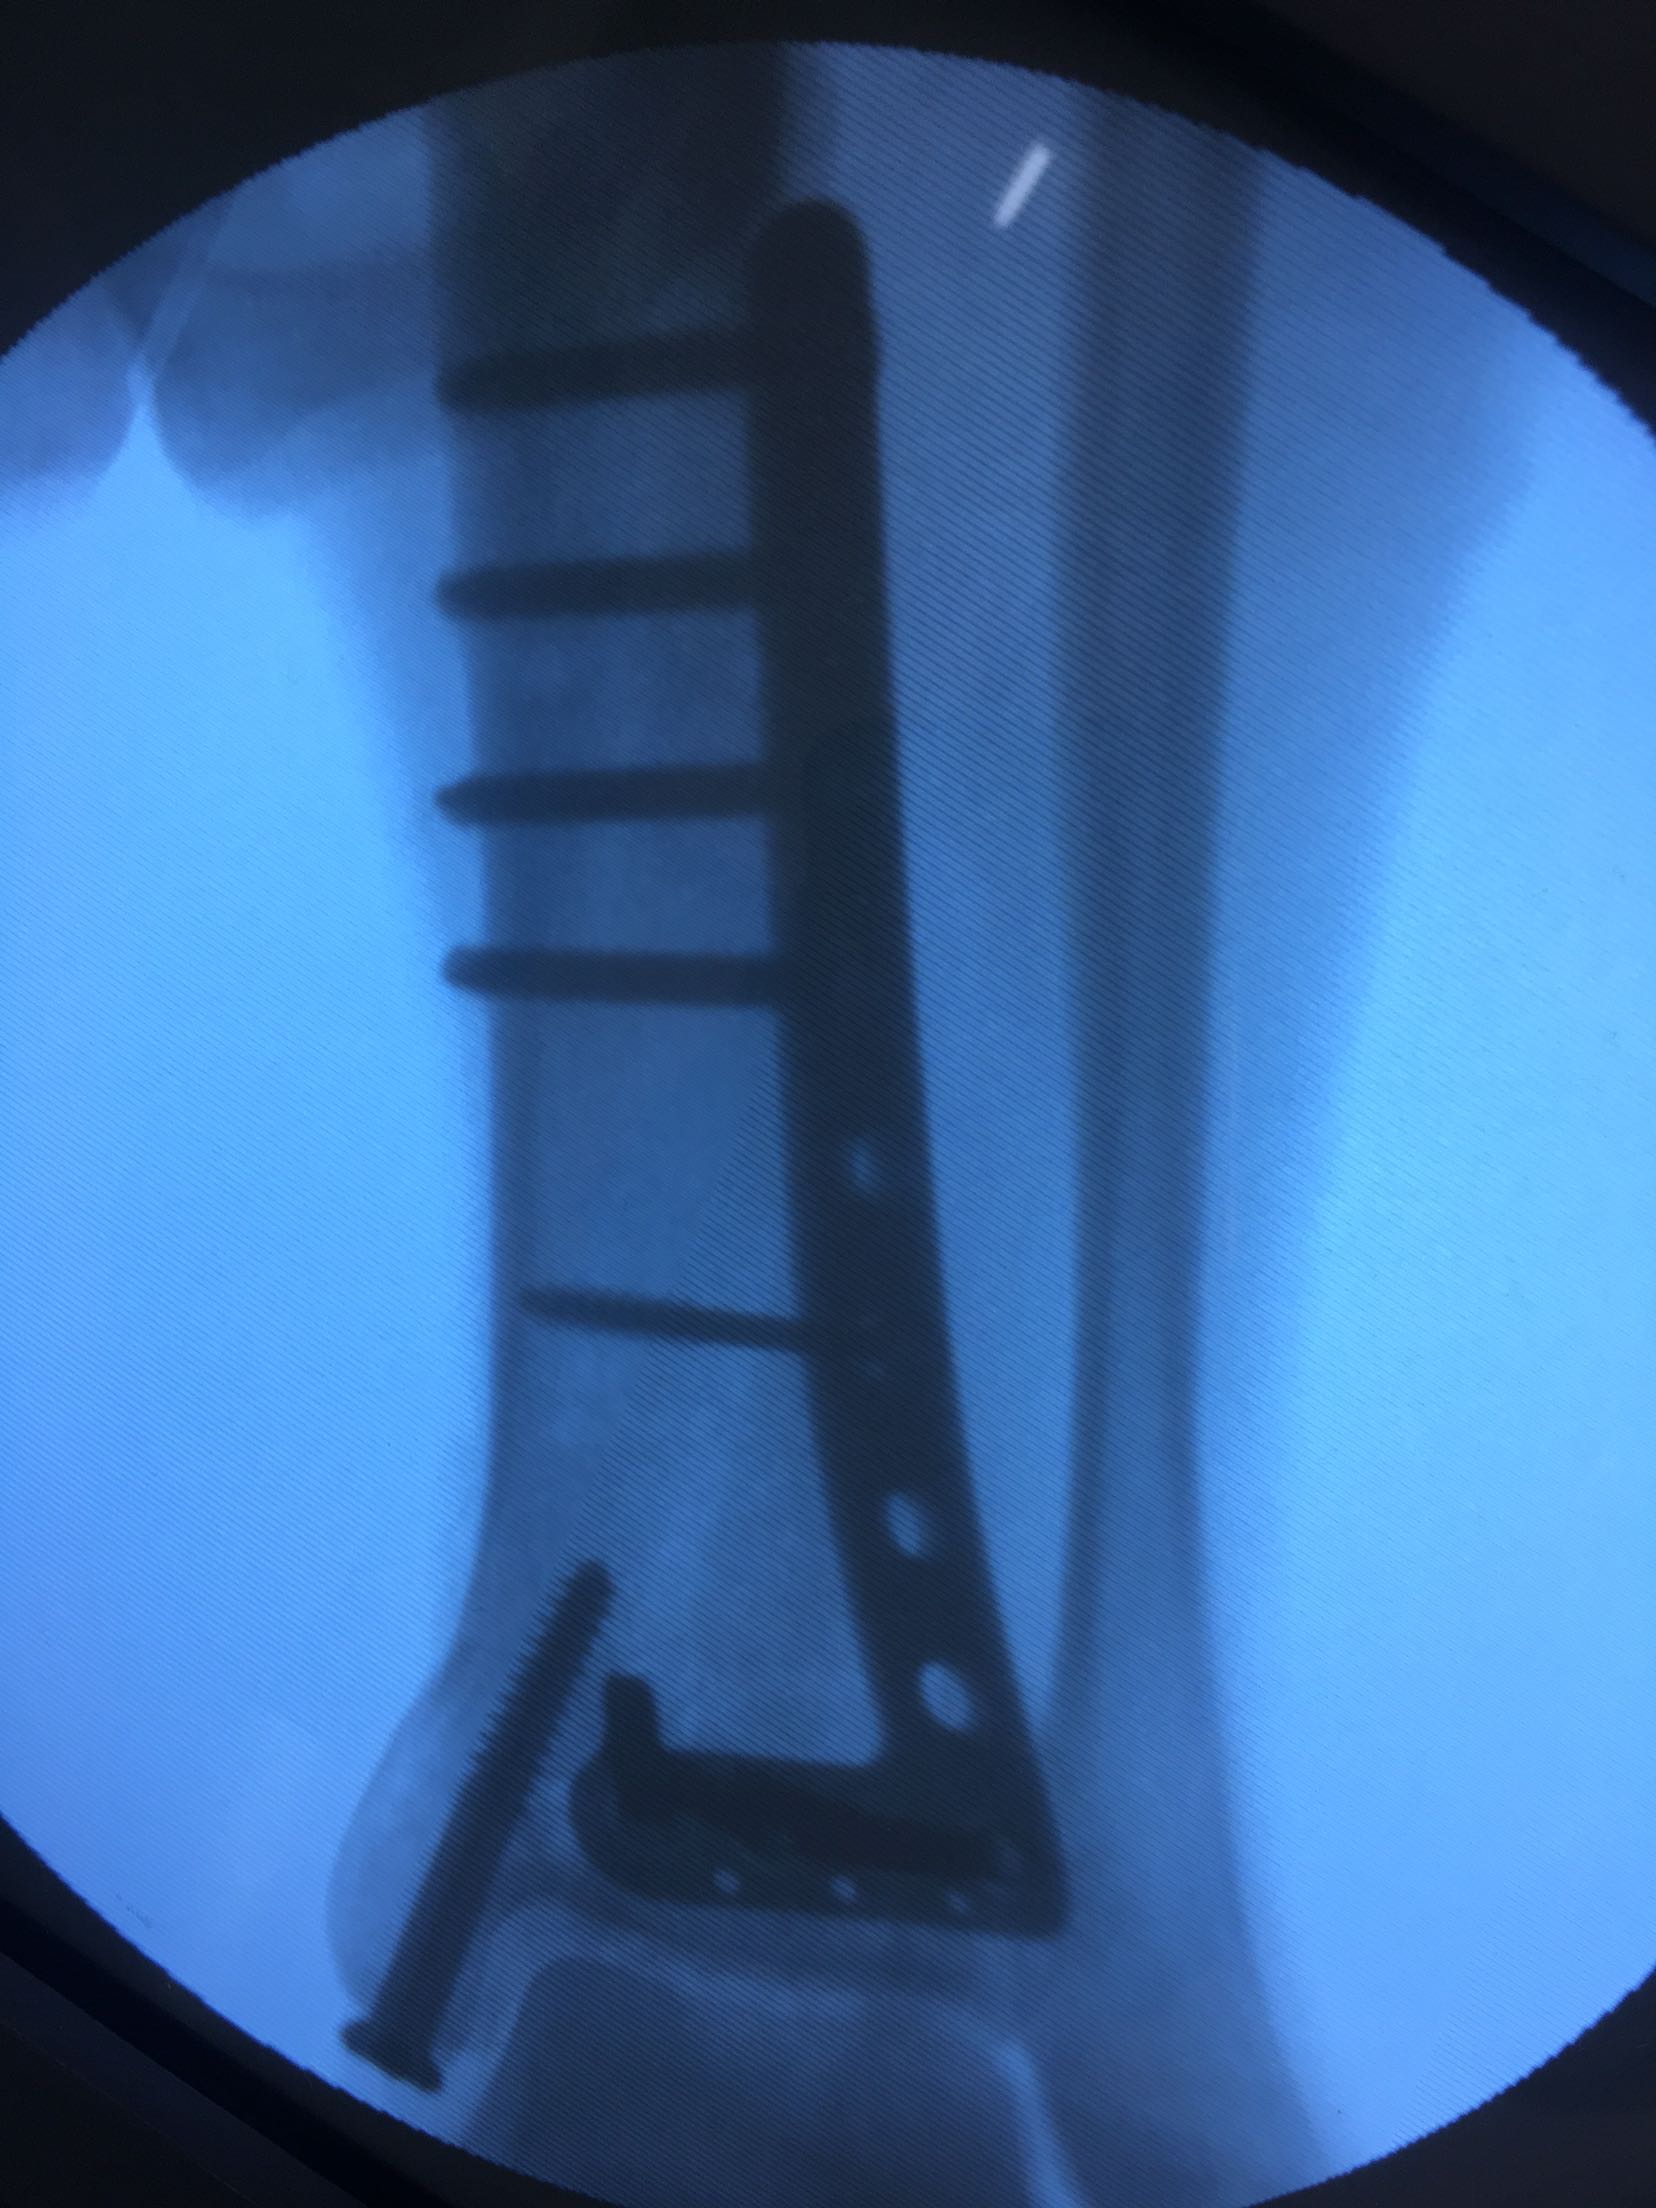

完善检查,在腰麻下行切复内固定术,术后制动,消肿抗炎处理。